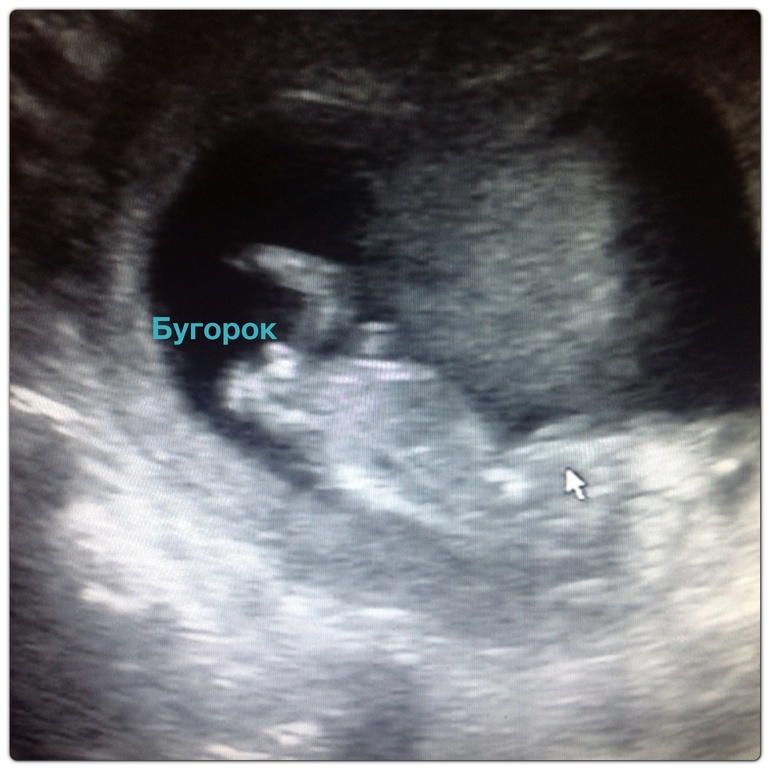

Результаты: УЗИ, КТГ, доплера, скринингаНу вот и мы пришли с узи. Сразу хочу сказать, что у меня какие-то неоднозначные чувства после узи в Арт-Меде у Мазырко. Рассказала все, показала все, НО много косяов, если честно. По ктр который у нас 57.74мм она мне ставит 11.5 недель, хотя по всем таблицам и у нее на компе вывело 12.3 недели, от куда у нее эта цифра ХЗ. Потом сердцебиение по узи на диске четко видно замеры 146 и она говорит 146, в выписке пишет 160, опять таки от куда???? Ребенок лежал очень неудачно и замерить было его сложно, твп ваще еле намерила и то на глаз, типа я вижу, что не расширенно и будет до 1 мм, пишет в выписке 1.2 мм. Больше замеров нет???? в Цире всегда пишут все и бедро, и бпр и так далее, тут ничего. Единственное стопу замерила 1.14мм большая. Фоток не одну не сделала, а в конце когда я поросила, мне ответили, что мне же диск записали типа этого хватит. Я настояла на фотке и мне распечатали 4 штуки одного ракурса, где нихрена не видно, хотя были хорошие кадры. Короче за 4000 думала будет больше. Ну и с уверенностью в 70% сказала будет девочка. Короче узи ни о чем, одно радует посмотрела мелочь свою, а она такая класная махала мамочке привет. Ну и фотки которые сделала с диска качество не айс. На первой фотке видно бугорок девочковый, но ракурс конечно не айс.

Наша ножка